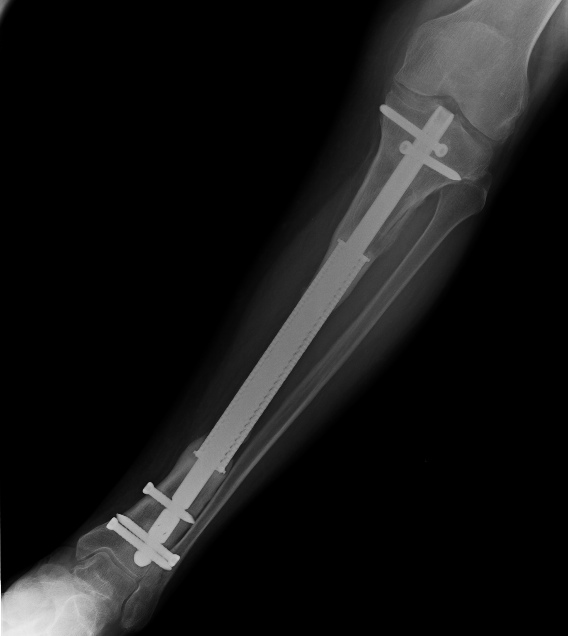

Я бы думал в сторону кейджей и внутрикостных блокируемых гвоздей. Аппаратом сначала все установить в желаемое положение, после чего размерять дефект имеющийся, плюс после освежения концов, и заказать кейджи. Зафиксировать с компрессией.

Что-то в этом роде. А.Ф.Лазарев может больше рассказать, он эту методику и показал нам. На предплечье не делали никогда, но почему бы и нет. И с крепким гвоздиком внутри должно сработать. Делали кейдж в МАТИ-ЦИТО, и не так давно в "Конмете", это в Москве.

Да вовсе не хотелось на это надеяться. Кейдж - это по замыслу пожизненный эндопротез. То есть уже отлично сработало, когда кость прорастает на концах только. Если получается по всей длине (это иногда бывает) - это такой бонус бесплатный, на это никто и не рассчитывал, поскольку и без полного обрастания уже хорошо. Коллеги, вы присланный пример увидели?

... полагаю, что если бы "никто не рассчитывал", строение кейджа было бы различным с концов и "в середине". А то вон их даже "иногда" чем остеотропным запоняют (картинки прилагаю).

Впрочем, согласен, онкопротезы (в т.ч. "растущие") как раз и являются той ситуацией, когда "отлично сработало" без прорастания.

Анатолий Федорович, дорогой, откликнись!: ты самый продвинутый в этой теме. Насколько сегодня часто используете эту методику, каковы наиболее отдаленные результаты и сколько их накопилось?

Строение у отечественных на концах и в середине действительно разное. У наших европейских коллег кейджи на всем протяжении одинаковые, потому что сетчатые, можно их кусачками подгонять под нужный размер. И еще это позволяет их подпружинивать, они не ригидные.